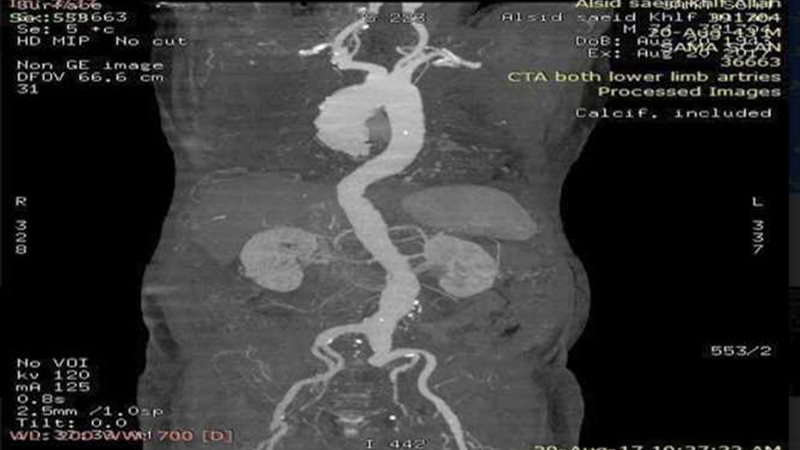

نجح فريق طبى بمستشفى النيل للتأمين الصحى بشبرا الخيمة في إجراء عملية تمدد بالشريان الأورطى، يبلغ حجمه ٧ سم لمريض بالقسطرة التداخلية دون اللجوء للفتح الجراحى.

ضم الفريق الطبى الأستاذ الدكتور أحمد خيرى استشاري جراحة الأوعية والدكتور أيمن فرجانى والدكتور هشام عطية أخصائيي الأوعية بالمستشفى، واستشاري التخدير الدكتور زكريا عبد العزيز، والدكتور عيد العطار مدير الشؤون العلاجية والدكتورة هالة نبيل نائب مدير المستشفى، وتحت إشراف الدكتور جمال حجاج مدير فرع التأمين الصحي بالقليوبية.

وقال الدكتور أحمد حجاج مدير عام المستشفى، إن المستشفى استقبل المريض فى حالة صعبة، وبعد إجراء الفحوصات اللازمة تقرر إجراء العملية، والتى استمرت قرابة الـ 3 ساعات وخرج المريض بعد مرور ٤٨ ساعة من العملية في حالة صحية مستقرة لاستكمال العلاج والمتابعة.